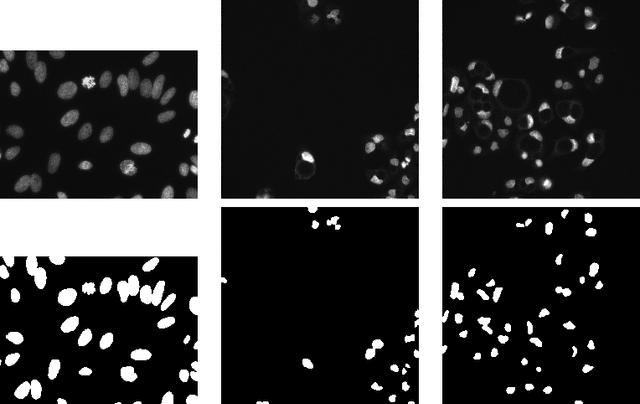

Abstract:Automatic segmentation of microscopy images is an important task in medical image processing and analysis. Nucleus detection is an important example of this task. Mask-RCNN is a recently proposed state-of-the-art algorithm for object detection, object localization, and object instance segmentation of natural images. In this paper we demonstrate that Mask-RCNN can be used to perform highly effective and efficient automatic segmentations of a wide range of microscopy images of cell nuclei, for a variety of cells acquired under a variety of conditions.